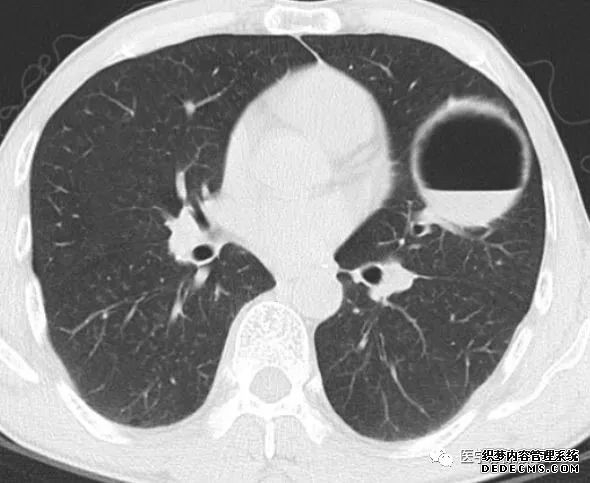

肺隔离症:易误诊为肺癌的占位性病变,肺穿刺禁忌!